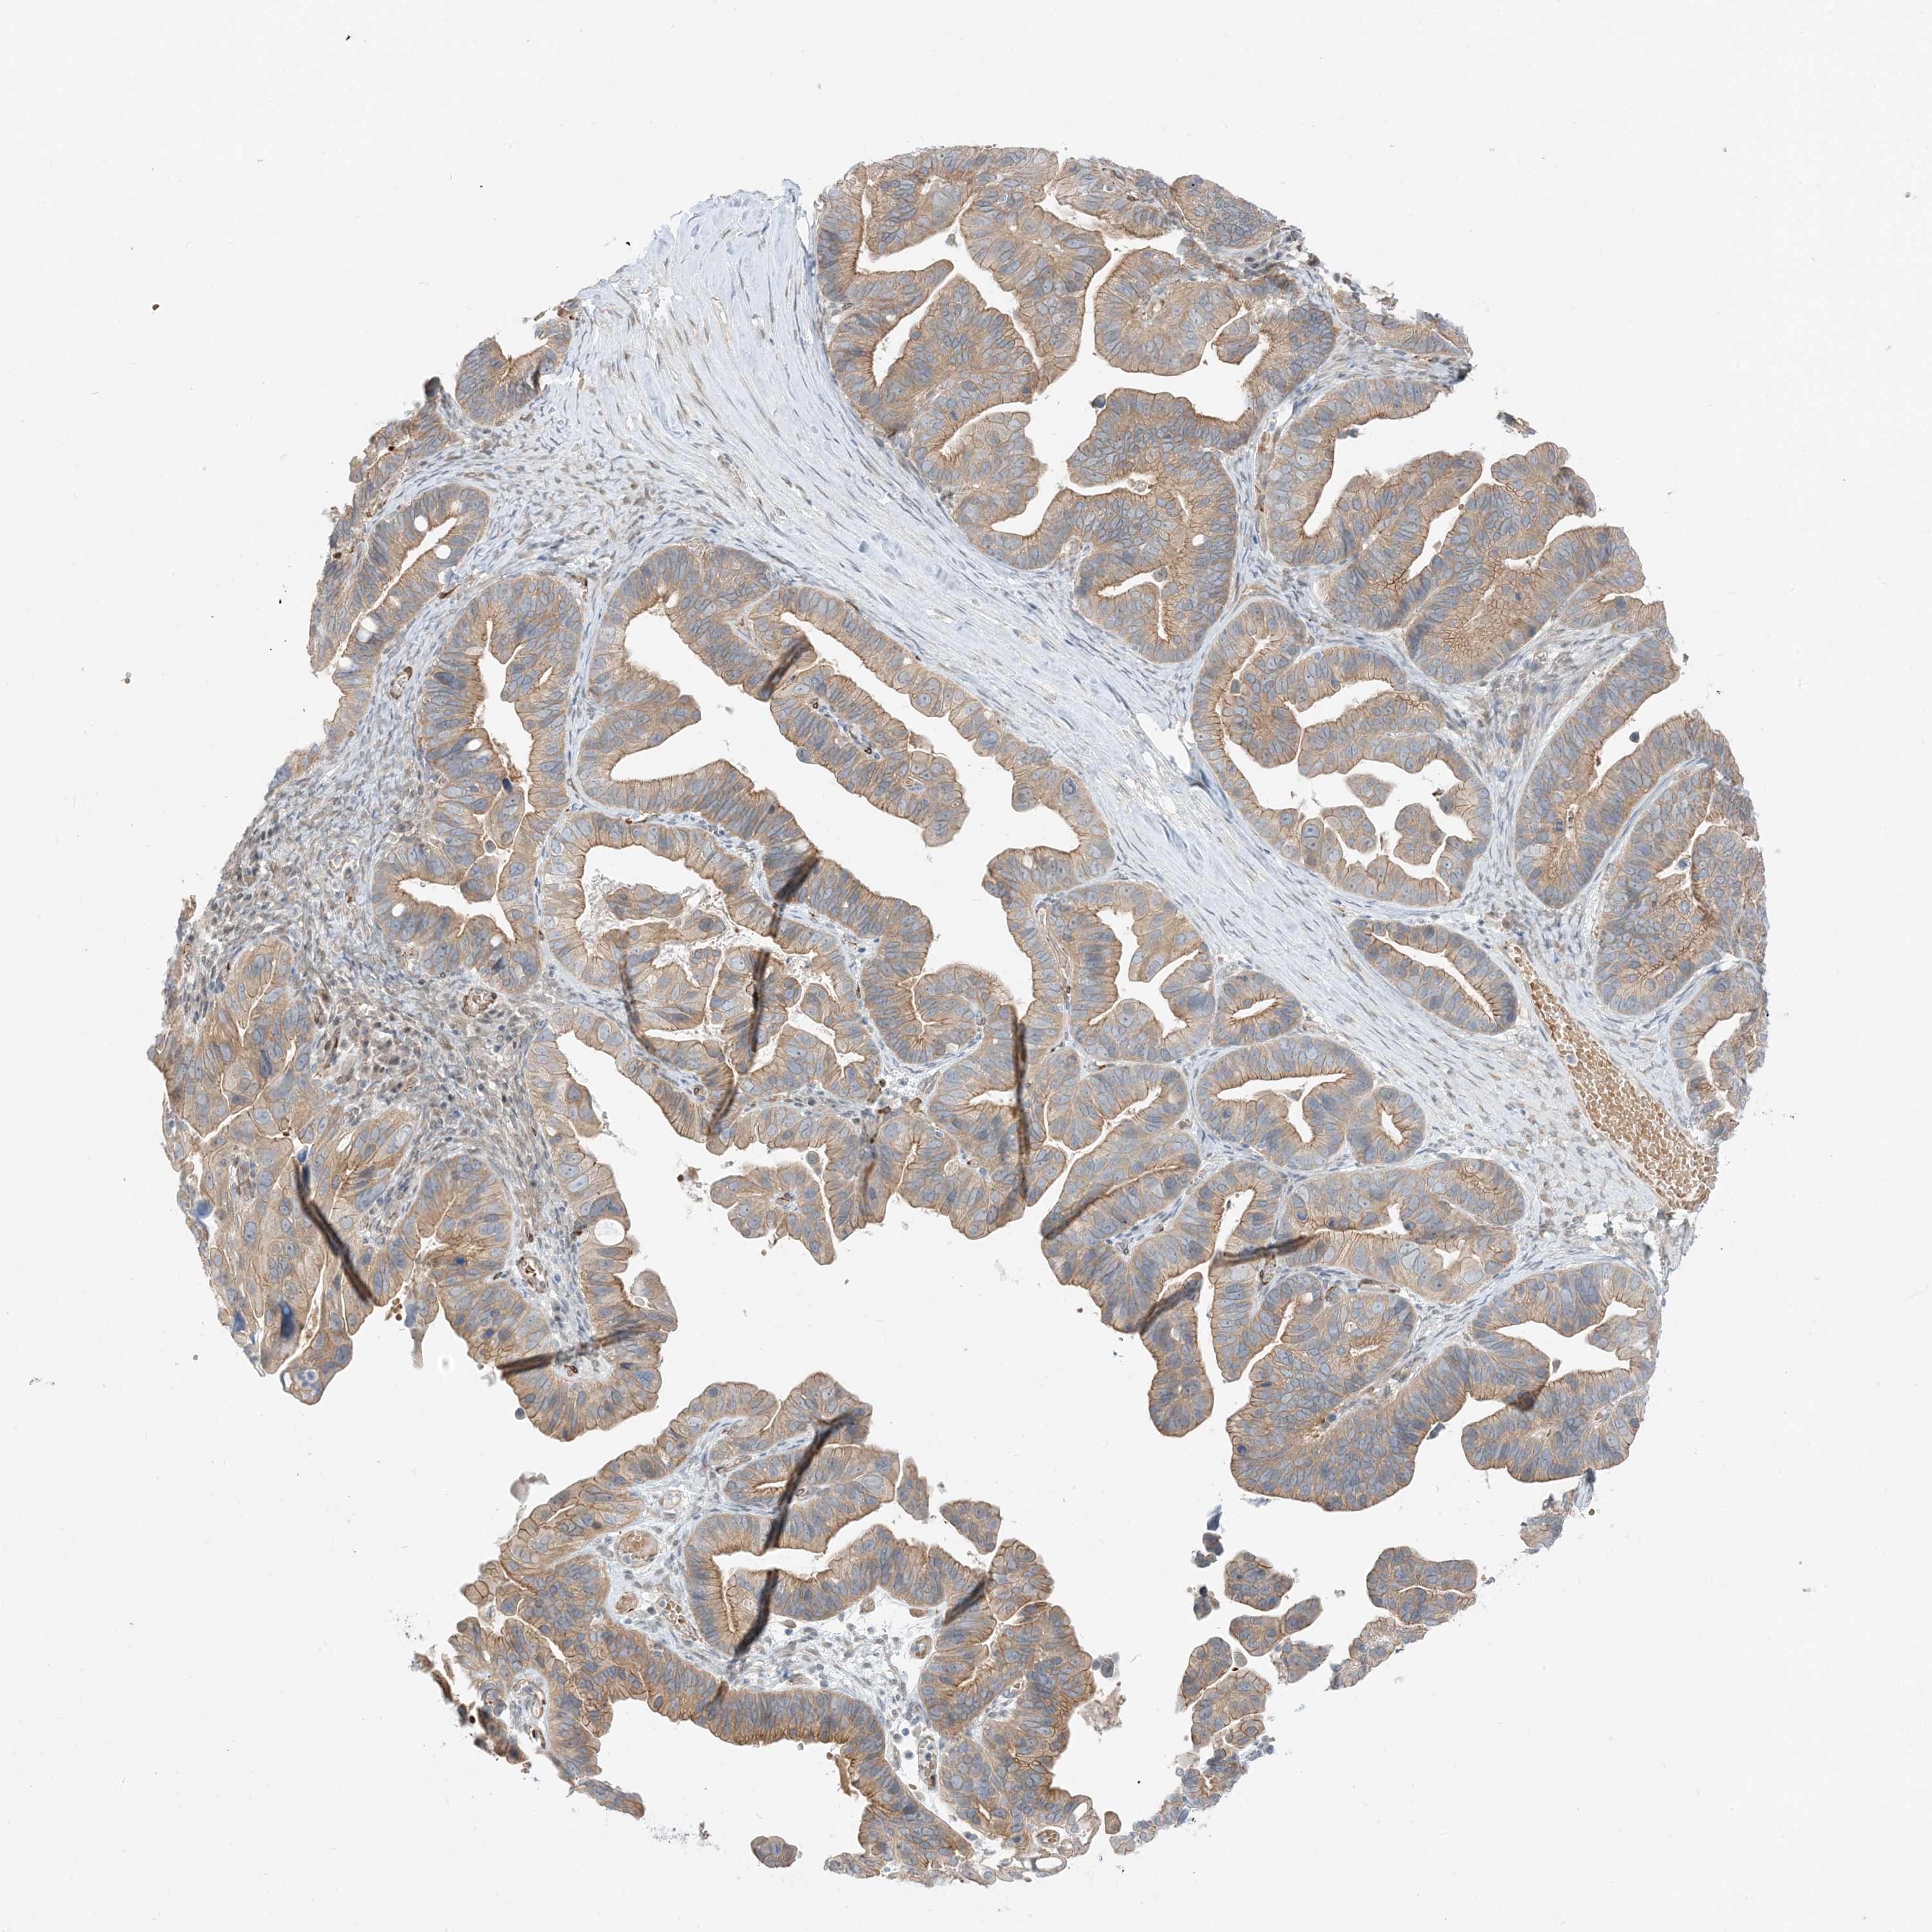

OVARIAN CANCER - Protein expressioni

A mouse-over function shows sample information and annotation data. Click on an image to view it in a full screen mode. Samples can be filtered based on level of antibody staining by selecting one or several of the following categories: high, medium, low and not detected. The assay and annotation is described here.

Note that samples used for immunohistochemistry by the Human Protein Atlas do not correspond to samples in the TCGA dataset.

Antibody stainingi

Antibody staining in the annotated cell types in the current human tissue is reported as not detected, low, medium, or high, based on conventional immunohistochemistry profiling in selected tissues. This score is based on the combination of the staining intensity and fraction of stained cells.

Each image is clickable and will lead to virtual microscopy that enables deeper exploration of all samples and also displays staining intensity scores, fraction scores and subcellular localization as well as patient and tissue information for each sample.

Antibody HPA035491

Staining

High

Medium

Low

Not detected

Intensity

Strong

Moderate

Weak

Negative

Quantity

>75%

75%-25%

<25%

None

Location

Nuclear

Cytoplasmic/membranous

Cytoplasmic/membranous,nuclear

Cystadenocarcinoma, serous, NOS

Carcinoma, endometroid

Cystadenocarcinoma, mucinous, NOS

Carcinoma, NOS